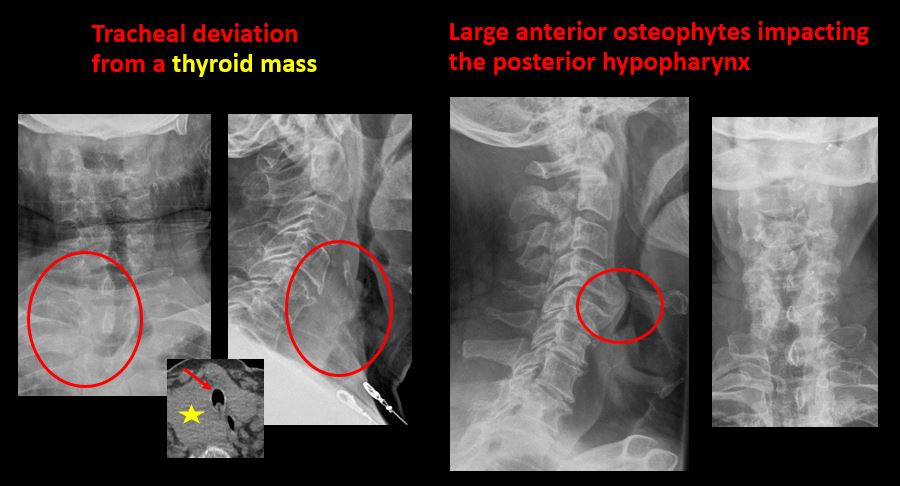

Section 1 Submit Findings C442 Findings Technique The craniocervical junction and/or C7-T1 are not entirely included on the exam. Yes No The exam is over or under penetrated. Yes No The exam is limited by overlying structures, bones or soft tissues, body habitus, patient positioning, support devices, or motion. Yes No Prevertebral and paravertebral soft tissues The soft tissues anterior to C1-C7 are widened or the prevertebral fat stripe is not seen. Yes No The paravertebral soft tissues are abnormally widened. Yes No N/A There is calcification, foreign body, abnormal air, or other abnormal density in the prevertebral or paravertebral soft tissues. Yes No Spinal alignment The distance between the basion and the posterior axial line is > 12 mm. Yes No The distance between the basion and the tip of the dens is > 12 mm. Yes No The atlanto-axial joint distance is > 2 mm on the lateral view. Yes No The distance between the dens and the lateral masses of C1 is abnormally asymmetrically widened on an odontoid or AP view. Yes No N/A The lateral mass(es) of C1 abnormally override(s) the articular pillar(s) of C2 on an odontoid or AP view. Yes No N/A The anterior vertebral body line, posterior vertebral body line, articular pillar line, and/or spinolaminar line is/are abnormal. Yes No The articular pillars or lateral masses, lamina, or other posterior elements are rotated or displaced into the spinal canal or the interlaminar clear zone of the spinal canal. Yes No The visualized spinous processes are malaligned on the AP view or distracted on the lateral view. Yes No There is reversal or straightening of the normal lordosis or abnormal angulation/curvature or motion of the cervical spine on frontal, lateral, flexion and/or extension views. Yes No Vertebral bodies, posterior elements, and base of skull There is a fracture or deformity of the base of the skull or occipital condyles. Yes No There is a fracture or deformity of the anterior or posterior arch of C1. Yes No There is a fracture or deformity of the lateral mass(es) of C1. Yes No There is a fracture or deformity of the dens or C2 vertebral body. Yes No There is a fracture or deformity of the pars interarticularis/articular pillars or other posterior elements of C2. Yes No There is a fracture or distraction of a C3-T1 vertebral body, transverse or spinous process, or other posterior element. Yes No There is evidence of an end plate avulsion or other fracture. Yes No There is displacement of a fracture fragment into the soft tissues, spinal canal, or interlaminar clear zone of the spinal canal. Yes No There is anterior wedging or compression of a vertebral body or end plate. Yes No There is evidence of an aggressive disease process manifest as a lytic, sclerotic, or destructive abnormality of a vertebral body, end plate, pedicle, lamina, articular pillar, transverse or spinous process. Yes No There is focal or diffuse abnormal mineralization. Yes No Disc spaces and facet joints There is distraction or focal widening of a disc space. Yes No There is anterolisthesis, retrolisthesis, subluxation, or rotational abnormality of a disc space. Yes No There is widening, rotational abnormality, or displacement of facets at any motion segment (e.g. locked or jumped, perched facets, or fracture dislocation). Yes No There is disc space narrowing with or without erosive or sclerotic changes of the end plates other than from degenerative change. Yes No There is facet joint narrowing or sclerosis other than from degenerative change. Yes No Additional soft tissues and bones (neck, airway, upper thorax, ribs) The included maxillofacial region, thoracic spine, ribs, or other bones of the upper thorax are abnormal. Yes No There is air or a foreign body or other abnormality in the soft tissues of the lower head, neck or upper thorax. Yes No There is an apical mass, thickening, pleural cap or effusion, or pneumothorax. Yes No N/A The airway is narrowed or displaced. Yes No There are post surgical changes of the bones or soft tissues of the lower head, neck, or upper thorax. Yes No There is an abnormality or complication of post-surgical hardware. Yes No N/A There are support lines or tubes in an abnormal position. Yes No Other findings There are degenerative changes or other existing conditions that might be contributing to symptoms which can or should be further evaluated non-emergently. Yes No